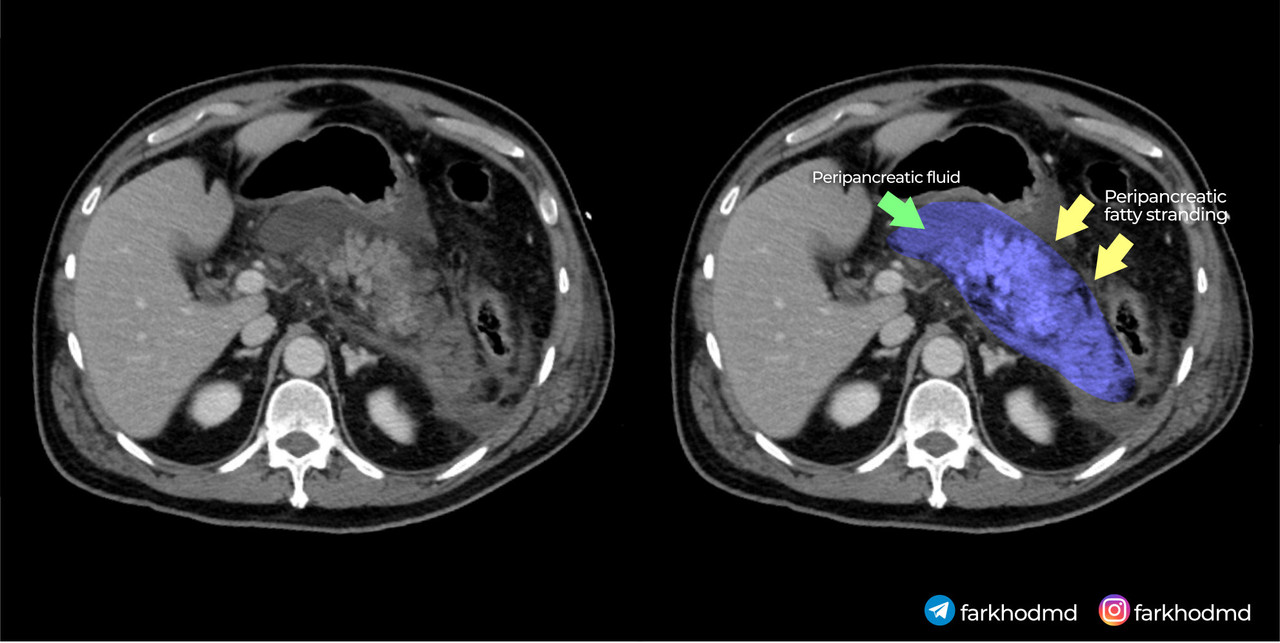

A 56-year-old man with a long history of heavy alcohol consumption presents to the emergency department with severe, persistent epigastric pain that started a few hours after a large evening meal accompanied by multiple beers. The pain radiates to his back, intensifies when supine, and is slightly alleviated by sitting forward. On examination, he appears acutely ill, with mild hypotension, tachycardia, and low-grade fever. His abdomen is markedly tender in the upper region, though without significant rebound tenderness. Laboratory tests reveal markedly elevated serum amylase and lipase. Serum glucose is also elevated. An abdominal CT scan is shown. Despite aggressive intravenous fluid resuscitation, pain management, and supportive measures, the patient rapidly deteriorates and dies within a short period of admission.

This patient’s presentation, marked by severe epigastric pain radiating to the back, elevated pancreatic enzymes, and hemorrhagic changes on imaging, reflects a severe acute inflammatory process within the pancreas. His longstanding heavy alcohol use sets the stage for pathophysiological alterations in the pancreatic acinar cells. Instead of enzymatic activation occurring normally in the intestinal lumen, the disruption of intracellular calcium signaling leads to premature enzyme activation inside the cell. As these enzymes become active prematurely, they begin digesting pancreatic tissue, causing inflammation, necrosis, and systemic complications. This cascade of intracellular events directly underlies the rapidly progressive and fatal outcome.

The key element driving this patient’s condition lies in the disruption of normal intracellular calcium signaling within pancreatic acinar cells. Under physiological circumstances, pancreatic enzymes like trypsinogen are secreted in an inactive form and only become active once they reach the duodenum. In the setting of heavy alcohol use, various factors, including altered intracellular calcium handling, trigger premature activation of these enzymes within the pancreatic acinar cell itself. Elevated intracellular calcium levels lead to the conversion of trypsinogen to trypsin prematurely, setting off a destructive cascade that causes autodigestion of the pancreatic tissue. This enzymatic injury results in necrosis of the acinar cells and subsequent release of proinflammatory cytokines.

These cytokines escalate the local inflammatory response and propagate tissue injury, contributing to systemic inflammatory response syndrome (SIRS) - which the patient most likely died from. As the tissue is digested, hemorrhage can occur due to erosion into blood vessels. Furthermore, damaged acinar cells produce less ATP due to mitochondrial injury, impairing cellular processes and fueling further necrosis. Laboratory evidence includes markedly elevated amylase and lipase, both of which are sensitive indicators of pancreatic injury. Additionally, hyperglycemia occurs due to impairment in insulin regulation when the pancreas is inflamed and damaged.